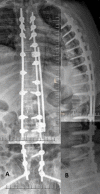

Methods: We report 2 unique cases of distal junctional failure (DJF) with worsening of neurology, secondary to nontraumatic fracture of a lower instrumented vertebra operated for thoracic canal stenosis without deformity. The first case had acute worsening of the Neurology during follow up and on evaluation, the supine CT and MRI scan revealed well decompressed spinal canal, no implant migration to the canal, no screw loosening, or rod failure. Supine sitting radiographs demonstrated DJK with Fracture and the patient underwent extension of fusion till the pelvis with 3-rod construct and interbody fusion, because of the instability at the L1 level.The second case remained neurologically stable for a month and then had an acute onset of back pain, sensory deficit, and urine incontinence. The supine-sitting dynamic radiograph done demonstrated L1 fracture with DJK at D12-L1 levels. The patient was counseled for extension of fusion, which was deferred by the patient.

Results: Patients in our series, had an acute worsening of neurological deficit within a month of posterior spinal fixation. Their supine imaging was almost normal, and the diagnosis of DJK with L1 fracture instability was possible only on a supine-sitting dynamic radiograph. Various factors like obesity, TL kyphosis, osteoporosis, etc. can be the attributing factors for the development of DJK CONCLUSION: A high index of suspicion is required for diagnosing nontraumatic fracture in long-level fusion patients with acute neurological worsening. The supine-sitting dynamic radiograph is an important diagnostic tool for DJF in patients having difficulty standing erect.